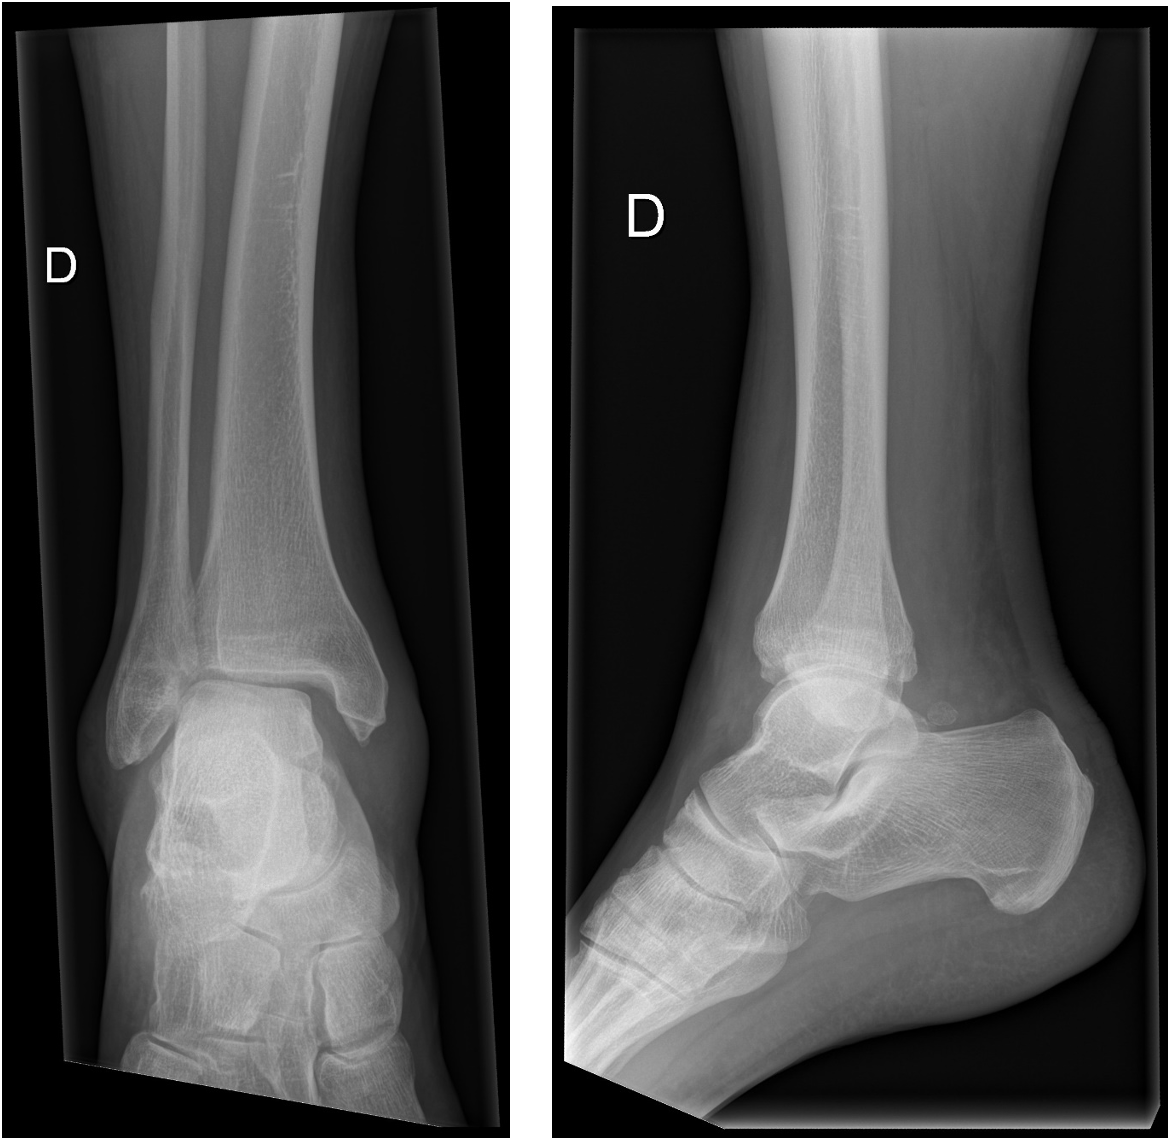

Un patient de 60 ans, en bonne santé habituelle, se présente aux urgences suite à une chute sur une plaque de glace. Il se plaint d'une douleur au niveau de la cheville droite, et explique avoir fait un ''faux mouvement'' avec son pied et sa cheville, mais ne peut pas décrire le mécanisme exact. A l’examen clinique, tu observes une tuméfaction bimalléolaire avec des douleurs importantes lors de la palpation et la pronation/éversion de la cheville. Il n’y a pas de troubles neurovasculaires.

Tu effectues des radiographies face et profil de la cheville droite :

Après avoir vu ces radiographies, comment envisages-tu la suite de la prise en charge ?